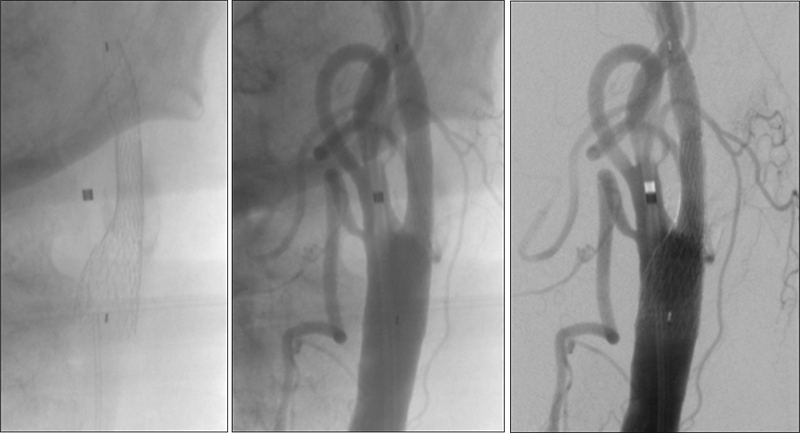

Εικόνα 1 και 2: Προσθιοπίσθια και πλάγια λήψη εγχύσεως στην αριστερή κοινή καρωτίδα. Εξεσημασμένη αθηρωματική στένωση (>95%) της εκφύσεως και του βολβού της αριστερής έσω καρωτίδος, με ελείμματα πληρώσεως (πρόσφατο θρομβωτικό υλικό). Η ροή υπεράνω της στενώσεως είναι ελαττωμένη και και καθυστερημένη.

01

02